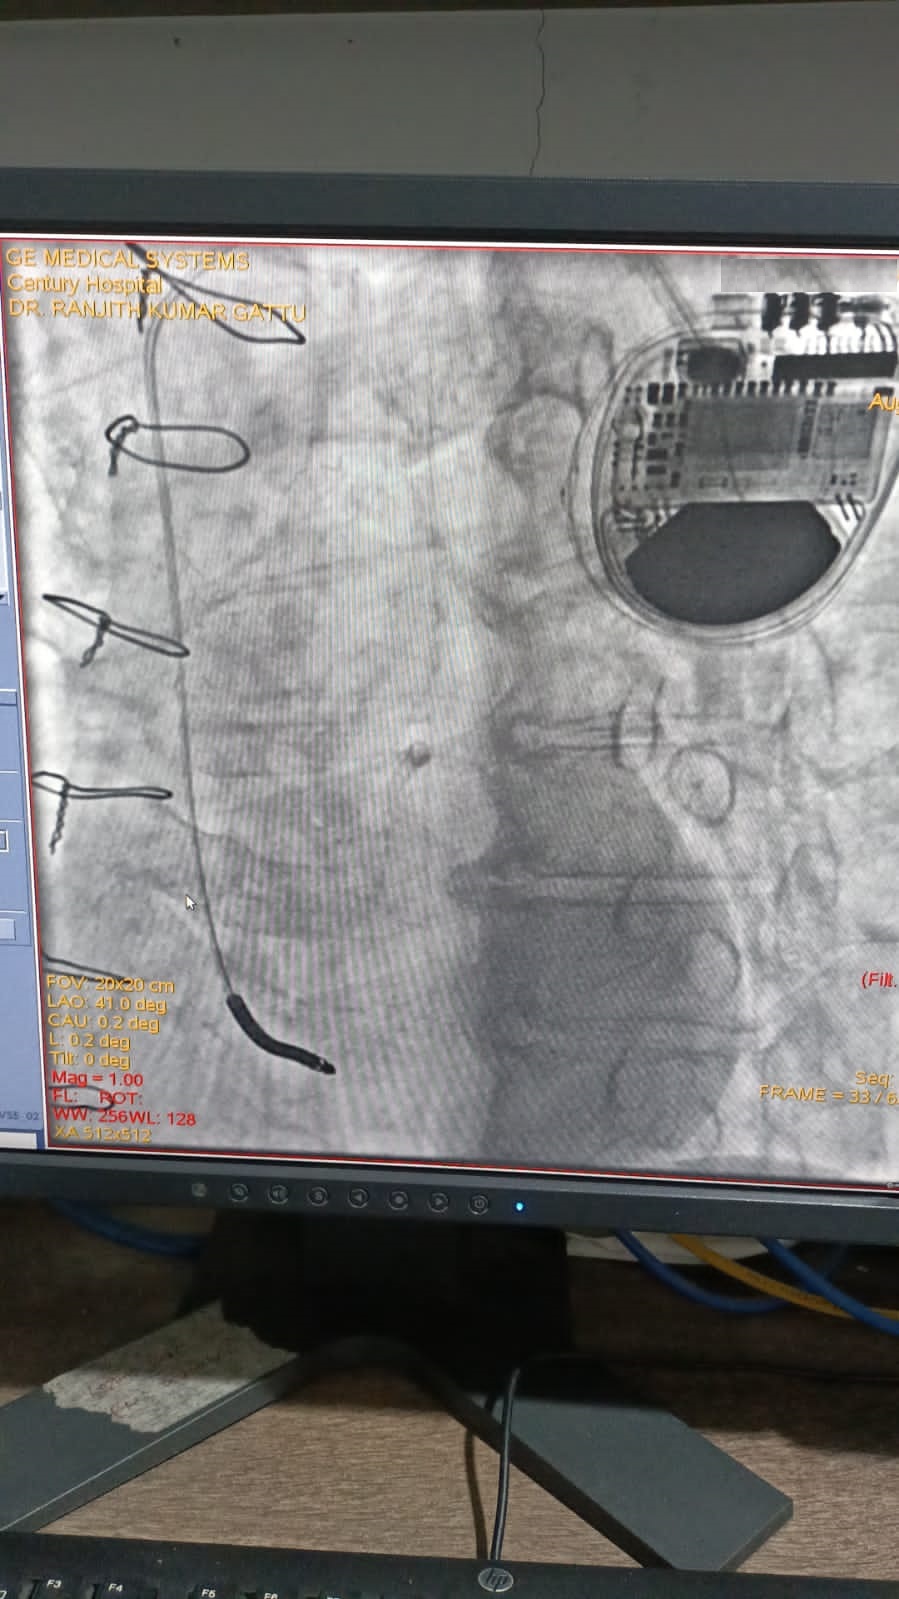

Catheter ablation of arrhythmias

Right Coronary Diseased Artery